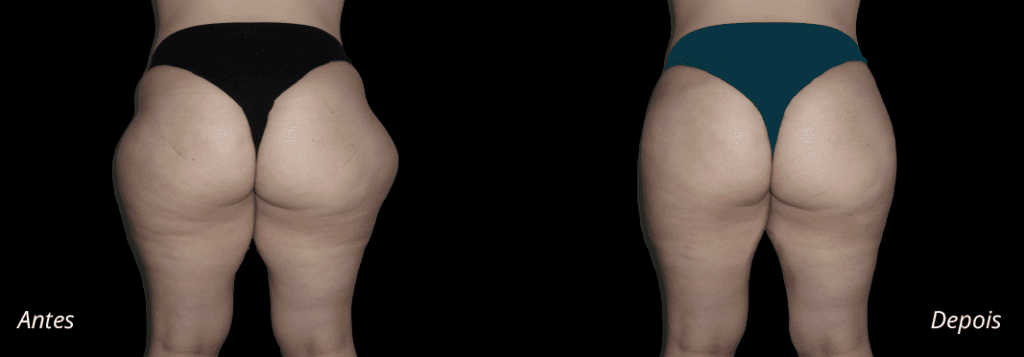

Imagens antes e depois